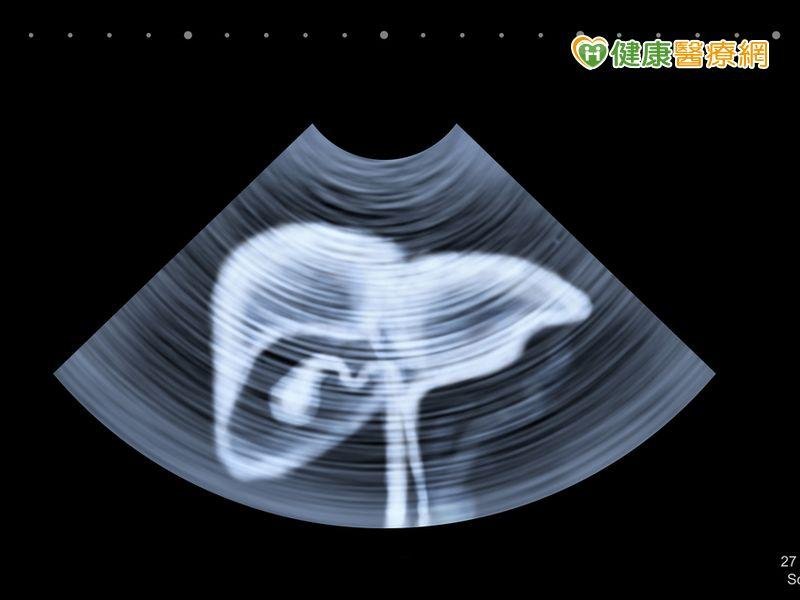

肝癌早期無症狀 腫瘤大小攸關存活率

自民國71年起,癌症一直居於台灣十大死亡原因的榜首,其中,肝癌的死亡率更是在癌症死亡原因的前兩名,每年新發現的個案逼近萬人。雖然非侵入性的腹部超音波是篩檢肝癌的利器,可診斷出小於1公分的肝臟腫瘤,但在臨床上,先進的篩檢技術並沒有使大型肝癌的個案數量降低,可見一般民眾對此疾病並無充分的警覺心。